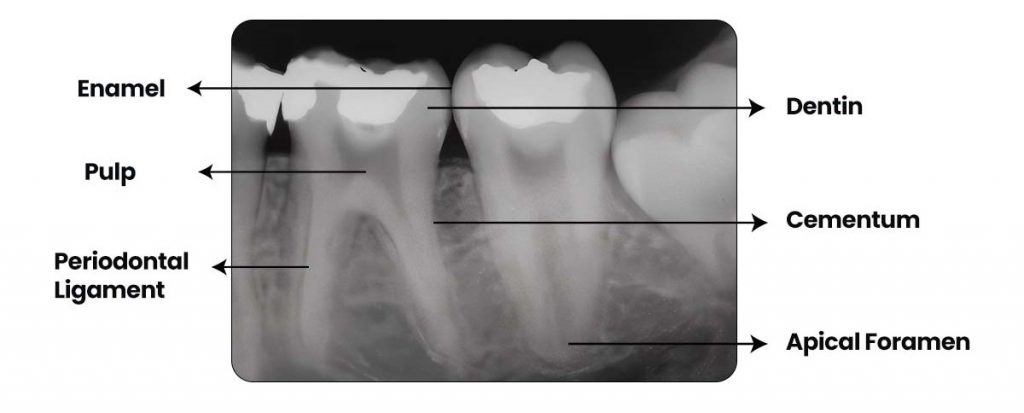

Step 3: Evaluate Crown Structures and Look for any of the following

- Interproximal caries (radiolucent notch near contact area).

- Overhangs, leakage of Restorative Margins.

- Fractures or Cracks of the crown.

Step 4: Analyze the Roots. Check for

- Number of roots (variation common)

- Root curvature

- Widened PDL space. Lamina dura should be continuous and radiopaque.

- Internal or external root resorption

Step 5: Periapical Region. Look for:

- Dark radiolucency → Possible abscess, granuloma, cyst

- Sclerotic bone changes

- Loss of the lamina dura

- Periapical radiopacities may indicate Cementoblastoma, condensing osteitis